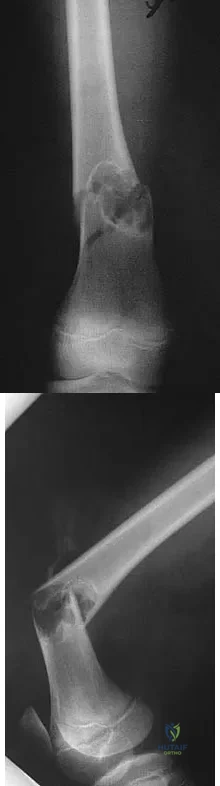

Question 20

An 11-year-old boy sustained an injury to his arm in gym class. He denies prior pain in the arm. Radiographs are shown in Figures 48a and 48b. What is the next most appropriate step in the management of this lesion?

Explanation